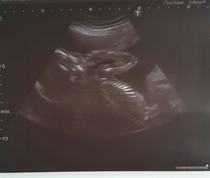

I don't know why it's not letting me add pics so here's another try now I'm on the website page instead... 1 of baby today and 1 of bump today at 20+2.

Lovely bump moon very cute scan too.

Omg moon that's got to be one of the best scan pics ever!!

Lovely pics moonlight

Moonlight that's such a lovely picture and I love your bump it's so neat.

Fab news Moonlight Smile I've found everything feels more positive after the 20-week scan. It's a nicer place to be generally!

moonlight congrats!! So happy for you and a little boy too! Snap!! And gorgeous pictures too!